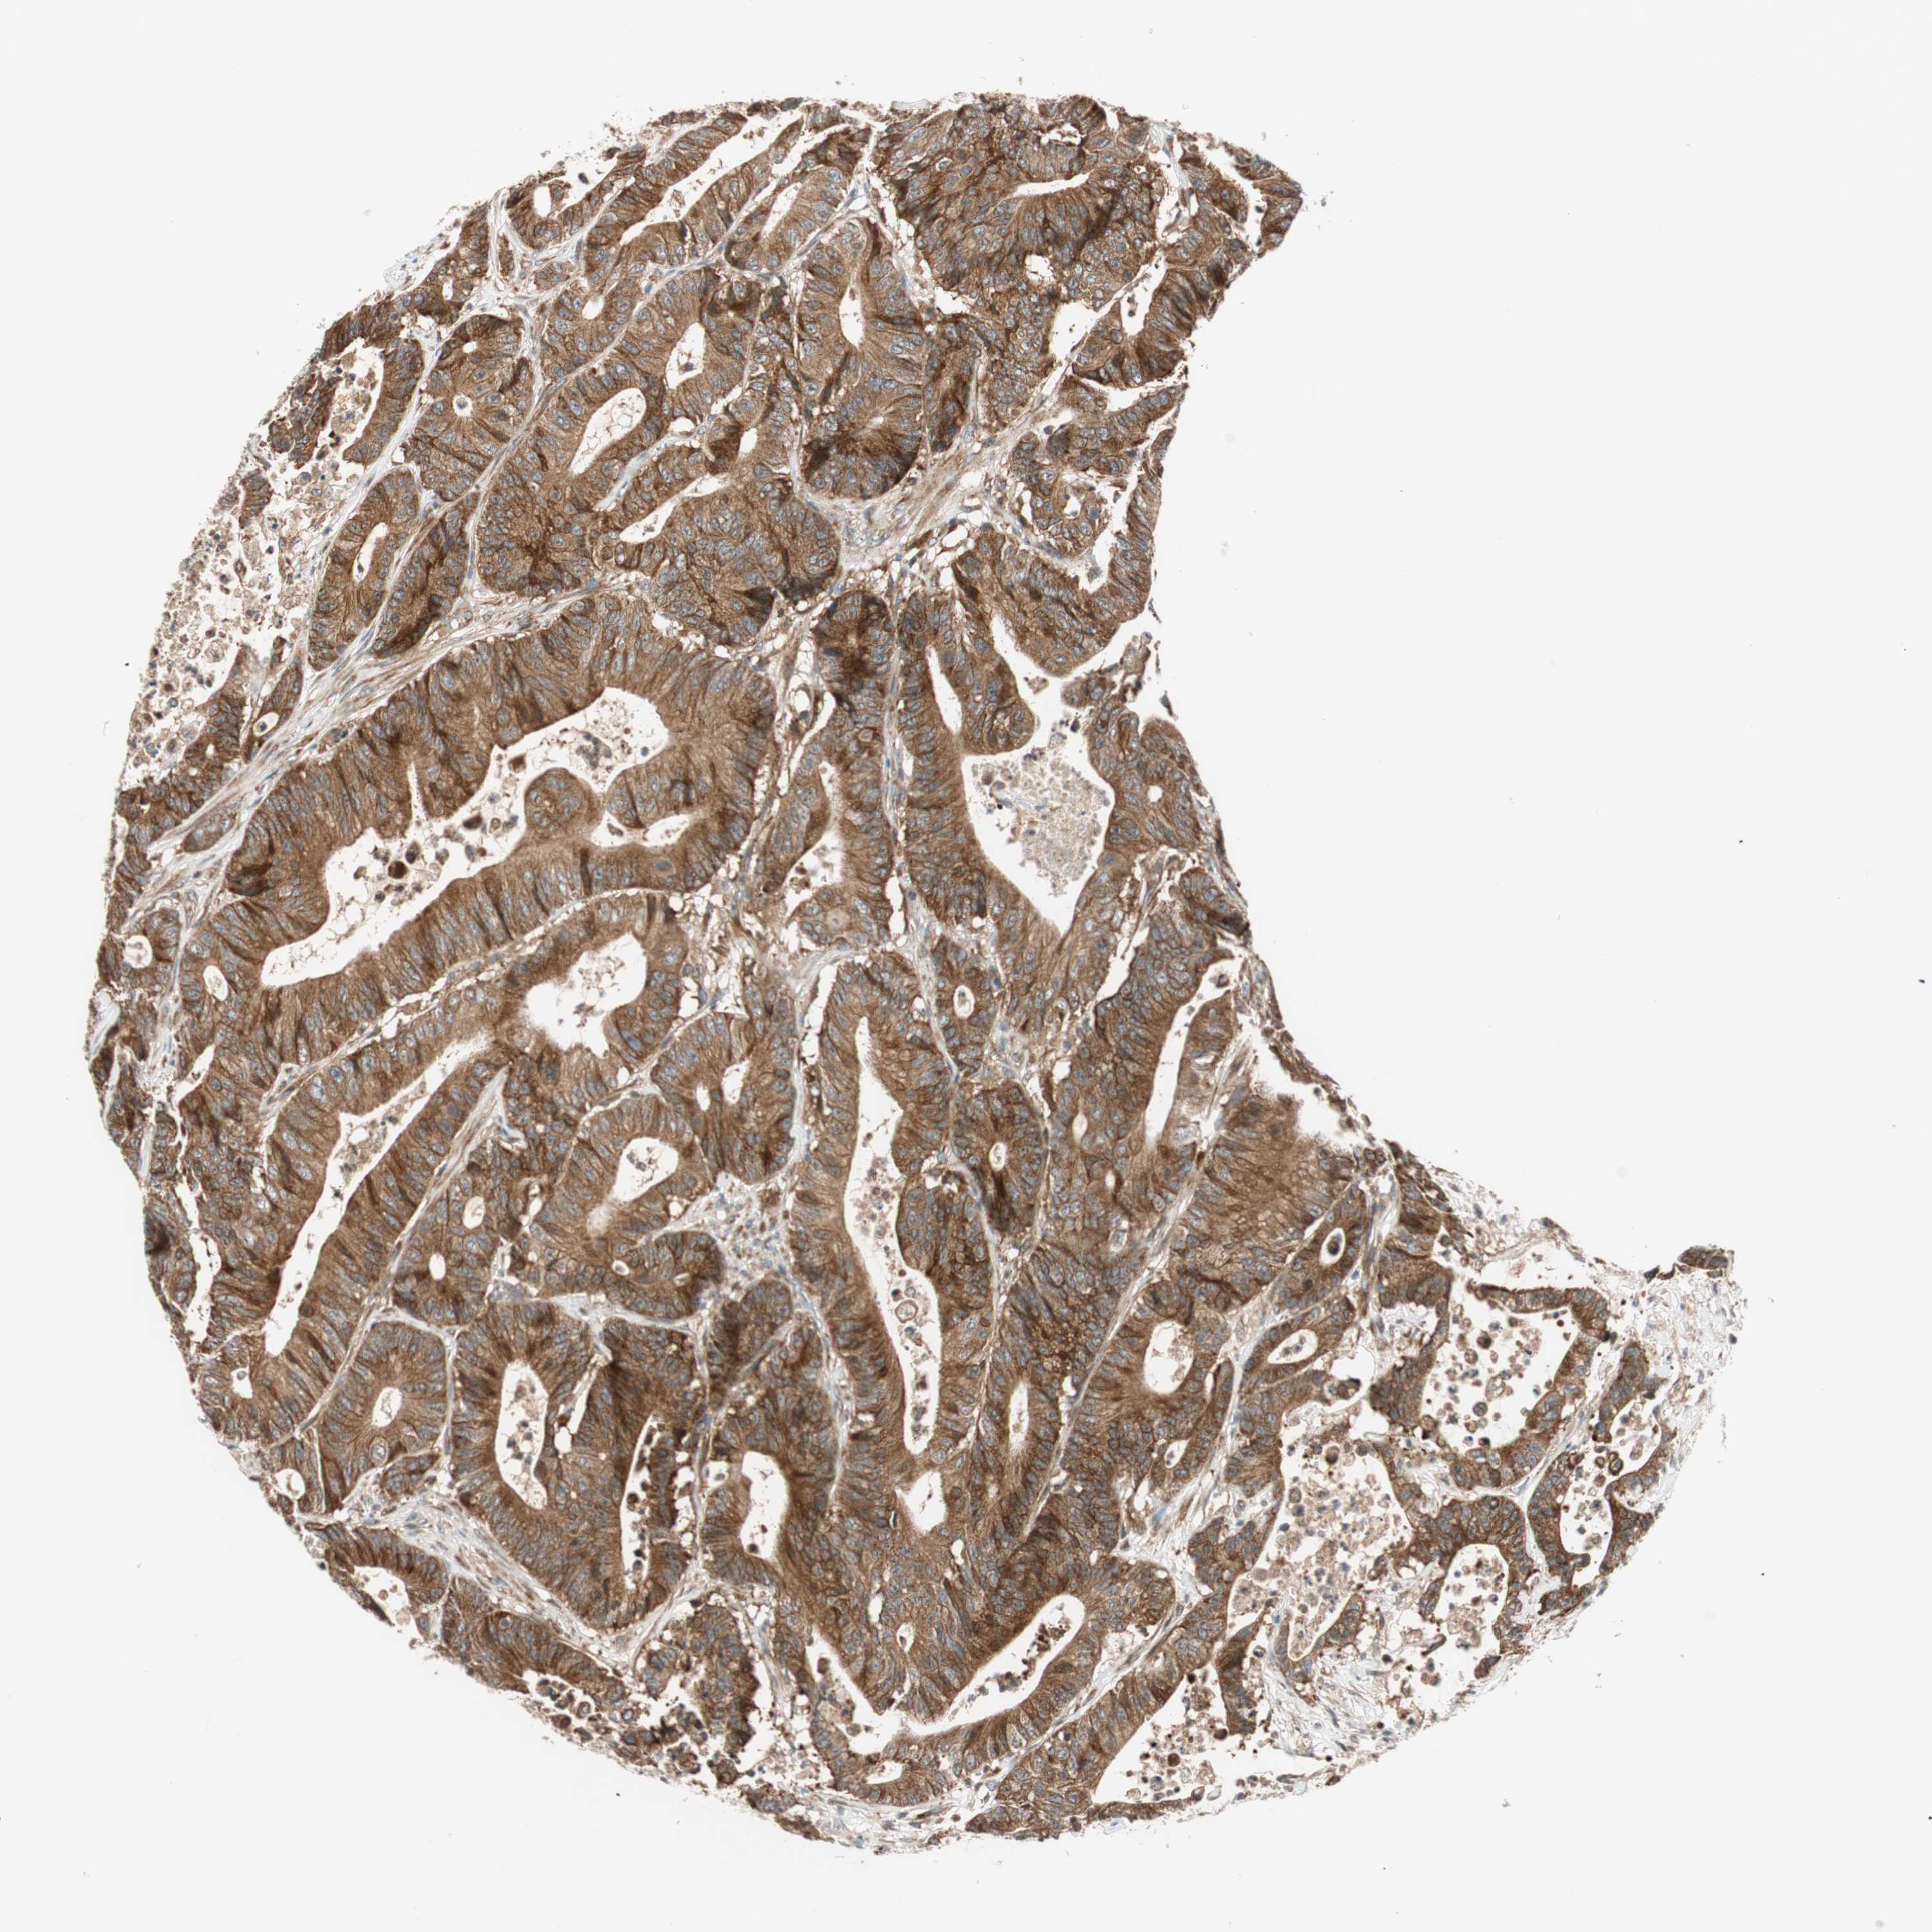

CANCER COLORECTAL CANCER Show tissue menu

Colorectal cancer

Human cancer

Colon adenocarcinoma